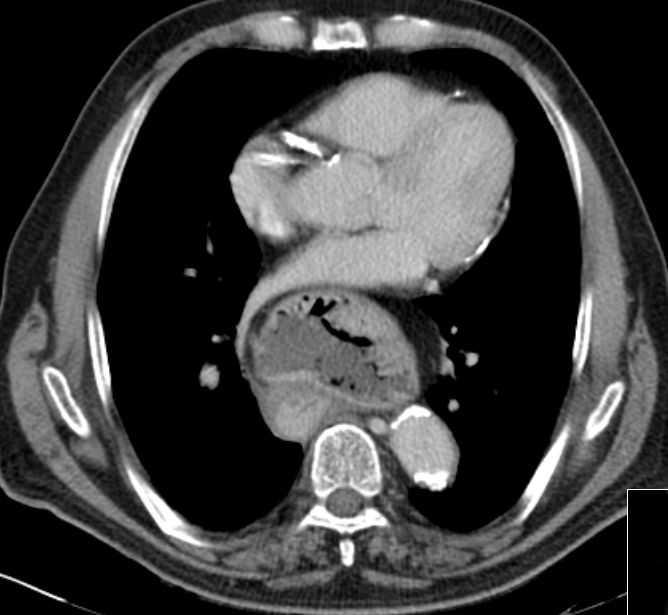

Hiatus - Hernie 83-jähriger Patient, der seit 2 Wochen Schluckbeschwerden mit unmittelbarem Erbrechen nach Nahrungsaufnahme hat. Das CT zeigt eine breite Zwerchfellhernie mit Teilen des Magens.

Die hintere Wand des intrathorakalen Magens ist verdickt: Adenokarzinom.

Der Ösophagus ist dilatiert und distal wandverdickt.